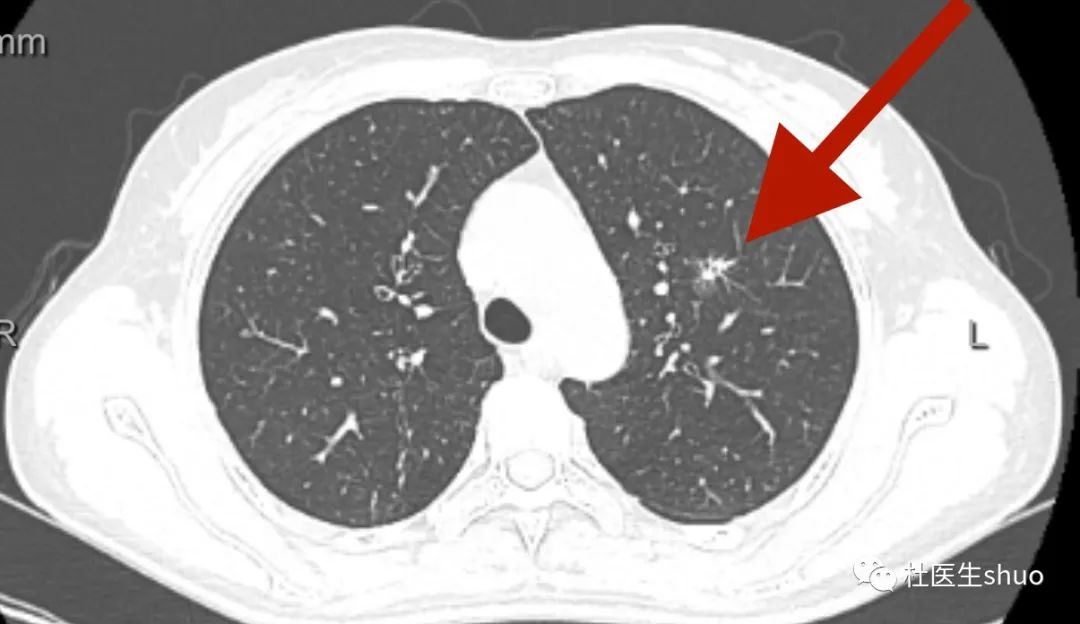

37岁男性右肺中叶部分实性结节